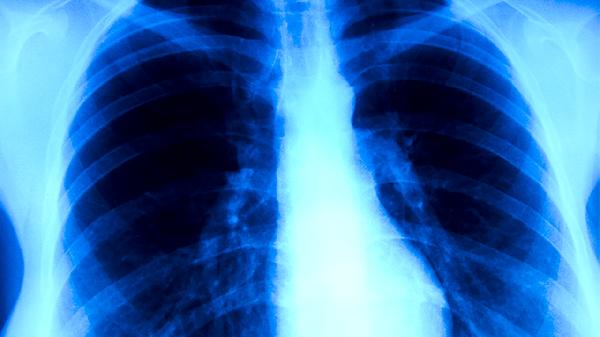

使用利福平、异烟肼等抗结核药物期间,可能降低痰涂片找抗酸杆菌的阳性率,因药物抑制细菌活性导致检测灵敏度下降。长期服用糖皮质激素可能掩盖肺结核的典型影像学表现,使病灶边界模糊或延迟空洞形成。免疫抑制剂如环孢素可能减弱结核菌素皮肤试验反应,出现假阴性结果。部分广谱抗生素可能暂时抑制结核分枝杆菌生长,影响痰培养阳性率。含钡剂或碘对比剂的药物在短期内可能干扰胸部CT检查的图像质量。

进行肺结核筛查前,应向医生详细说明近期用药史,包括处方药、中成药和保健品。结核菌素试验前通常需停用免疫抑制剂数周,痰检采集宜在晨起空腹时进行。若正在接受抗结核治疗,需结合临床表现与多次检查结果综合判断疗效。特殊人群如孕妇、肝肾功能异常者用药时,更需注意药物与检查的相互作用。